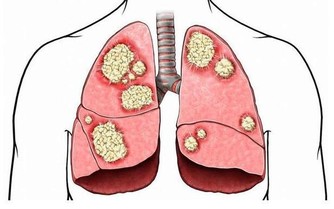

人體的腸道有8到10米長,平均每隔3.5公分就有一個彎折,即使是每天都排便,還會存在很多食物殘渣的堆積,它們在細菌的作用下乾結、腐敗、發酵,日積月累,這些食物殘渣最終形成厚達5-7毫米,重達5-6公斤的黑色、惡臭、有毒的物質,這些就是俗稱的宿便。

宿便中可產生22種毒素,這些毒素被腸道吸收,通過血液循環到達人體的各個部位,導致面色晦暗無光,皮膚粗糙、毛孔擴張、痤瘡、皺紋。

魔芋是世界上最優質的膳食纖維,具有很高的持水性,有較大的吸水性,持水大約相當於自身的1.5—2.5倍。從而可以增加人體排便體積和速度,減輕直腸壓力和泌尿系統壓力。可緩解膀胱結石,腎結石,使毒物迅速排出體外;同時,魔芋可以抵制腸道中產生的致癌物質的腐生菌生長,減少次生膽汁酸產生,減少致癌物質與結腸接觸的機會,產生丁酸,清除自由基—OH,從而防治胃癌及結腸癌等疾病。